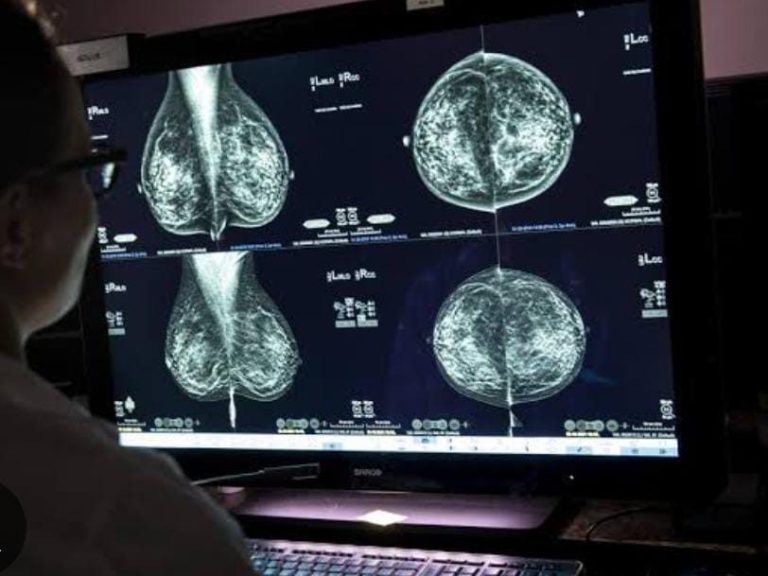

Cursos para comprender la correcta interpretación de placas ultrasonidos y radiografías, por medio de placas reales de mastografia, ultrasonidos, radiografias, etc.

Mastografía Digital

Enfoque en la mastografía con casos reales para un aprendizaje efectivo.